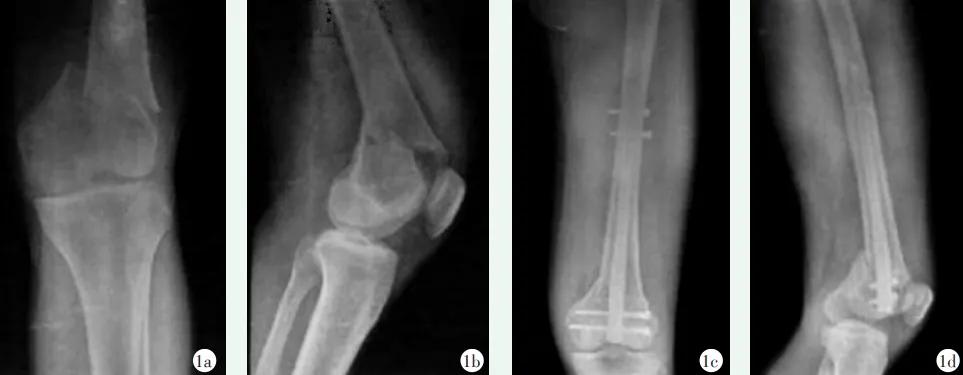

图5 患者,男,32岁,车祸导致左侧股骨远端A2型骨折,行逆行髓内钉内固定治疗 1a,1b:术前正侧位X线片示左侧股骨远端A2型骨折 1c,1d:术后复查X线片示内固定稳定,复位良好。